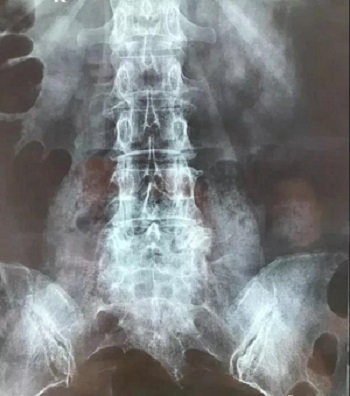

十三、CT片子的翻拍,请参考磁共振片子的翻拍,道理是一样的,先拍一张整图,然后再分区域进行拍摄。